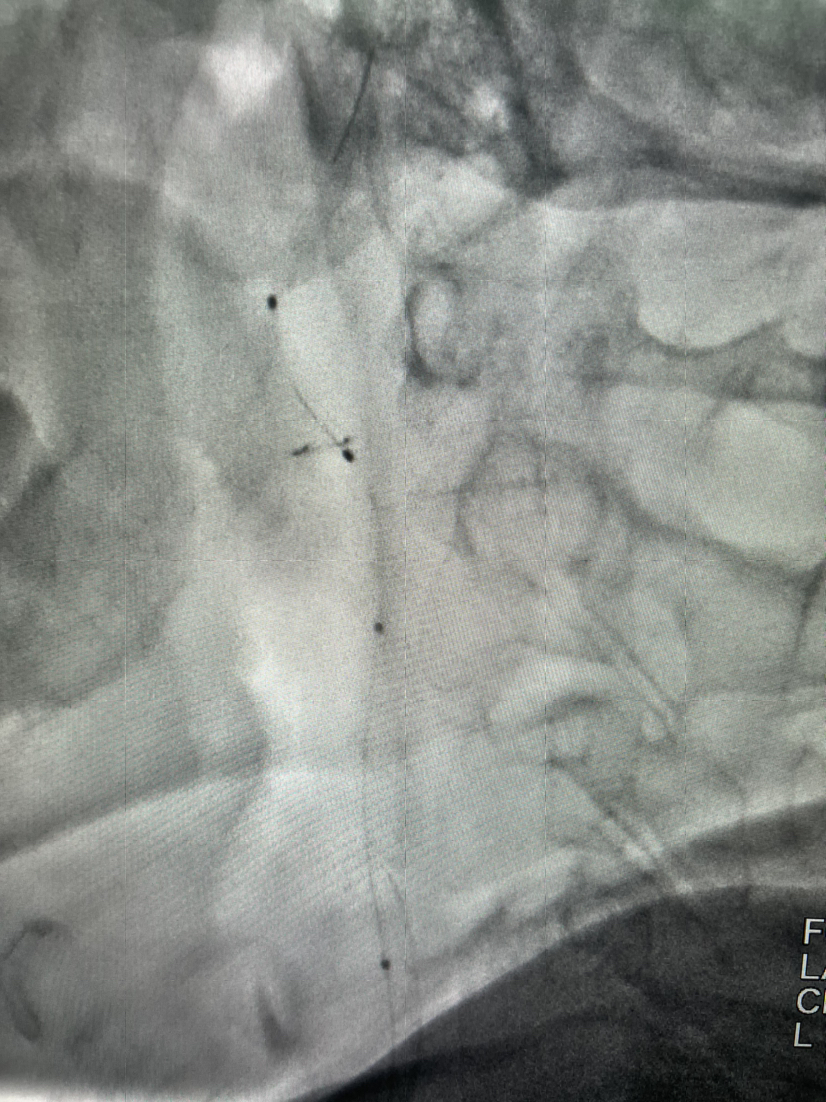

Spider保护伞到位